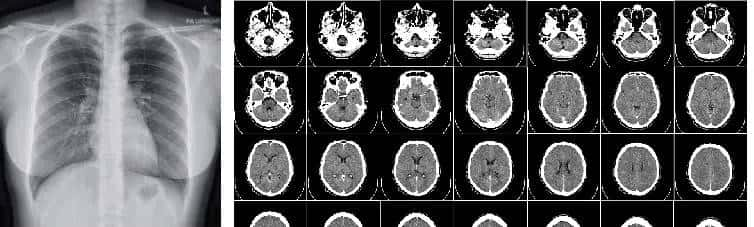

与同样用X射线拍的DR照片不同的是,CT生成的照片是三维的,因此往往会看到这样的切片照片:

由于CT机拍照时,而是将X射线分切成1mm-10mm的小切片分别照射,并通过环绕目标周围360°高速旋转扫描,目标再配合纵向进出射线生成最终的3D模型照片:

CT照片里一排排的图片就是每个X射线切片的成像结果。